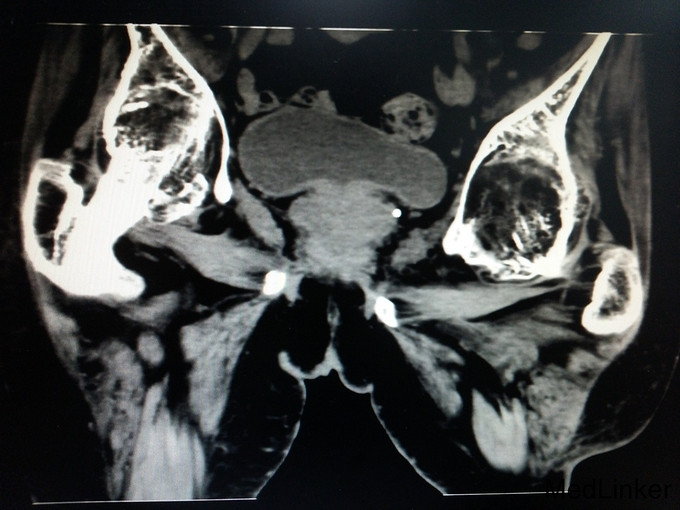

诊断:强直性脊柱炎(累及双侧髋关节) 患者腰骶部活动受限,影像学提示患者双侧骶髂关节间隙消失,且患者HLA—B27异常,强直性脊柱炎诊断明确。患者双髋关节间隙消失,活动度丧失,累及髋关节诊断明确。具有明确手术指症。患者既往关节鳞屑病,现控制稳定,经皮肤科会诊后排出手术禁忌症。由于经济稳定,患者及家属决定分次手术,本次手术暂行右侧人工全髋关节置换术。

讨论: 经验:强直性脊柱炎累及双髋的患者行全髋关节置换术时,显露及找到髋臼是手术的重点和难点。 1.显露。由于髋关节强直,失去活动度,助手在不能旋转大腿,造成显露困难。我们的做法是先充分显露小粗隆,沿小粗隆上方约2cm处截骨(一般常规于小粗隆上方0.5-1cm处截骨),充分离断头颈部,此时助手可通过内旋患肢,充分显露。下一步再按常规行小粗隆上截骨。 2.清除瘢痕组织。此类患者由于长期髋部强直,活动受限,周围往往会形成瘢痕挛缩,多以内收肌紧张常见。故显露的过程需彻底清除周围瘢痕组织。术中安装假体后测试关节各方西活动,若内收肌紧张,需行内收肌松解。 3.找髋臼。由于强直性脊柱炎累及髋关节需行关节置换的患者,往往头与髋臼已经发生融合,术中很难判断髋臼。若贸然凿除所谓的股骨头,很可能会破坏髋臼壁。故找髋臼时性循序渐进,逐渐凿骨找到髋臼。CT片显示头与髋臼底之间仍有间隙存在,故可推断圆韧带仍存在,这也是这类患者的特点。故逐渐凿除股骨头时,到达圆韧带的层面时就找到了髋臼底。此时可开始磨钻磨锉髋臼。从小号开始依次增大号数。 4.骨质。强直性脊柱炎的患者因长期服用激素类药物,骨量丢失较正常人较多,故髋臼骨质疏松明显,所以磨搓髋臼时需反转,防止骨量过度丢失,磨穿髋臼。 不足:1.术中由于患者左髋强直,摆放手术体位受限,不能维持身体中立位,身体后仰,术中安放臼杯时未能把握合适的前倾角度。 2.假体的选择。由于术前未认真评估股骨髓腔的形态,导致术中按常规选择股骨假体柄后,出现假体柄打入困难。该患者股骨髓腔形态呈烟囱型,最好选择直柄,打入后可更贴合,方便骨长入。